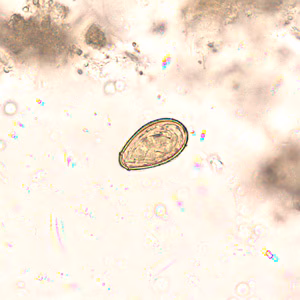

Eggs of Opisthorchis spp. in wet mounts.

Diagnosis is based on microscopic identification of eggs in stool specimens. However, the eggs of Opisthorchis are practically indistinguishable from those of Clonorchis. The adult fluke can also be recovered at surgery.